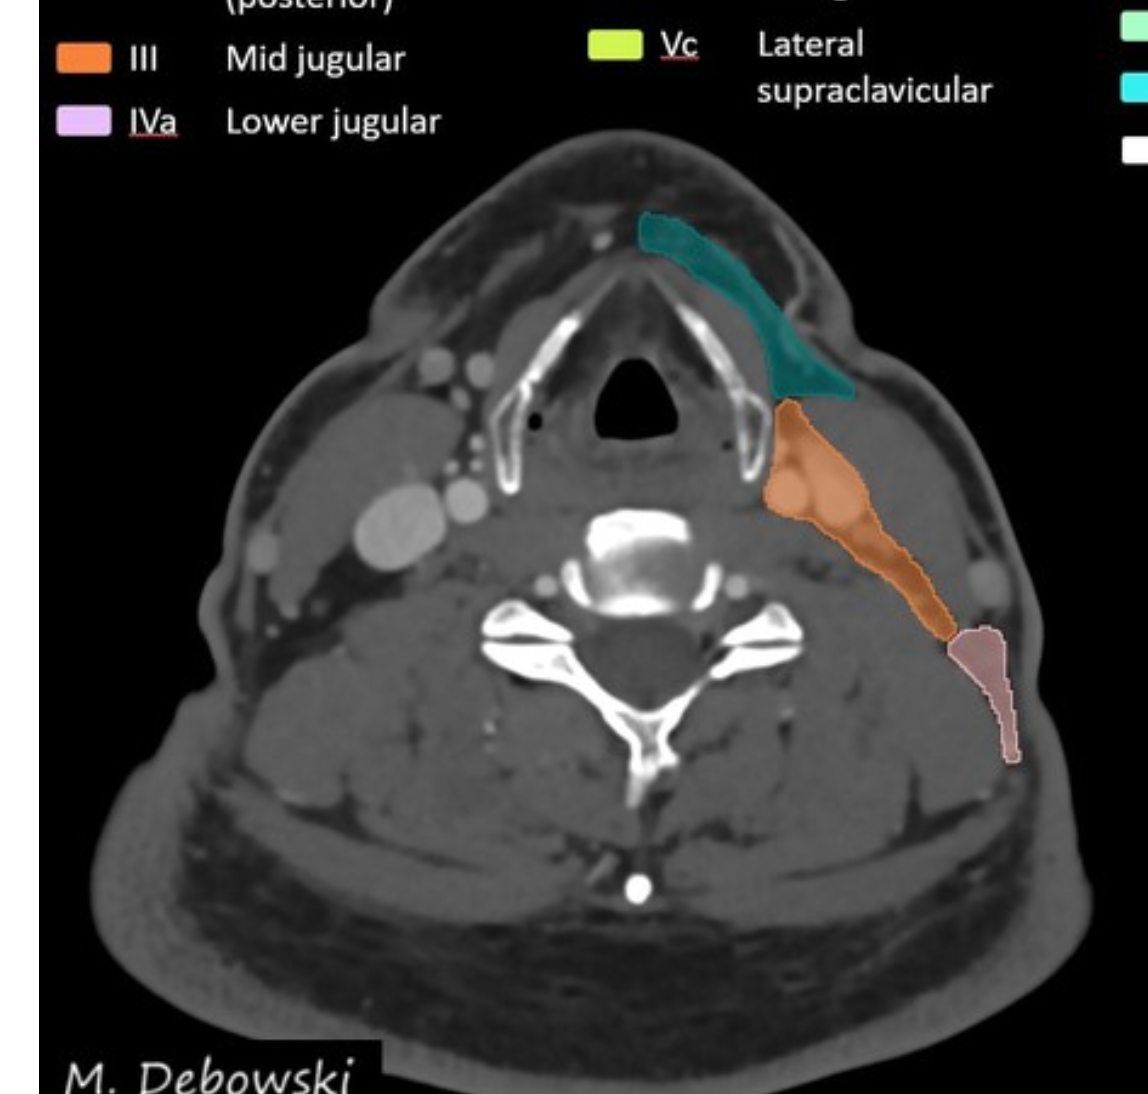

Level III lymph nodes

Boundaries

superiorly:

inferiorly:

anteriorly:

posterolaterally:

medially:

There are two sublevels:

Level IV lymph nodes Boundaries

Level IV: lower internal jugular (deep cervical) chain

superiorly: inferior border of the cricoid cartilage

inferiorly: level of the clavicle/manubrium

anteriorly: anterior border of the sternocleidomastoid muscle

posterolaterally: oblique line drawn through the posterolateral edge of the sternocleidomastoid muscle and the lateral edge of the anterior scalene muscle 2

medially: medial border of the common carotid artery

includes medial supraclavicular nodes including Virchow node 1